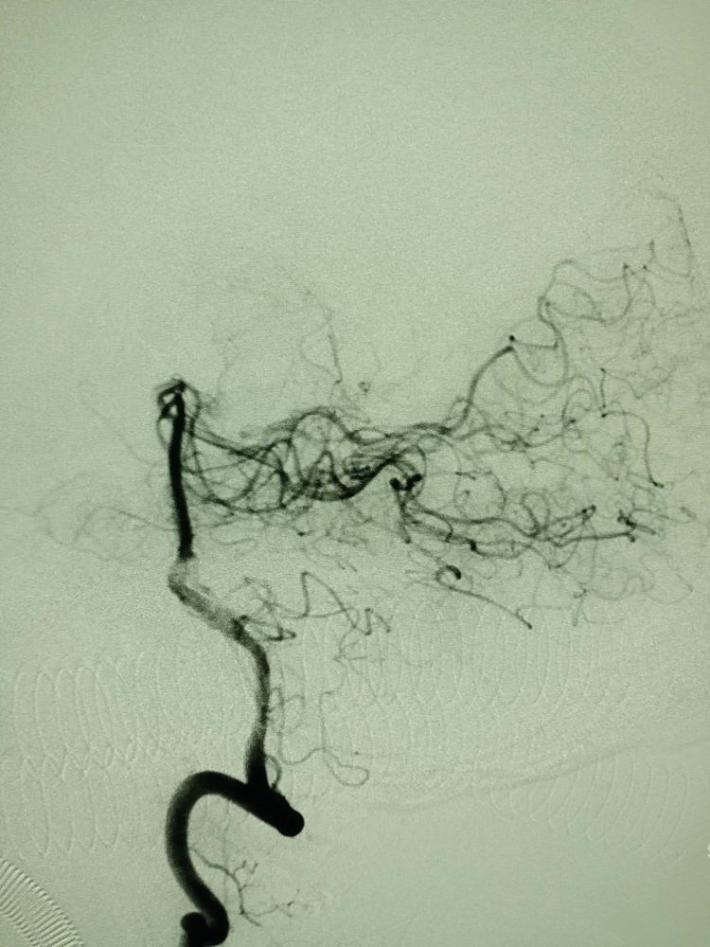

左侧颈总动脉造影提示:左侧大脑中动脉闭塞,考虑责任病变。

微导管超选至闭塞血管的远端,手推造影证实在真腔。

国产取栓支架尼科4mm*20mm成功打开,前向血流恢复。